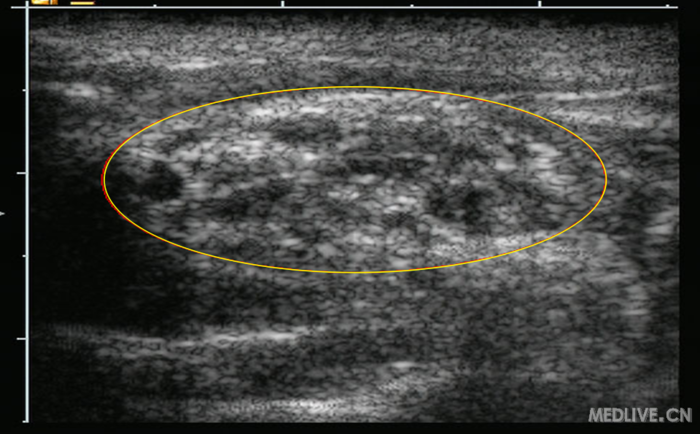

三、超声图像特点:

锁骨上臂丛神经,臂丛神经横断面呈低回声,黑色,周围是三角形的高回声的神经鞘(白色),内侧是圆型搏动环低回声锁骨下动脉,锁骨下动脉位于高回声的第一肋上方。神经鞘内的神经分支形成5-6个黑色圆环,周围被高回声环(纤维膈)包裹分隔成独立的室(这就是锁骨上臂丛神经阻滞单点注药起效慢和阻滞不全的原因)。斜角肌肌肉呈低回声(黑色),下方也可见到呈高回声(白色)的胸膜顶神经分支情况。